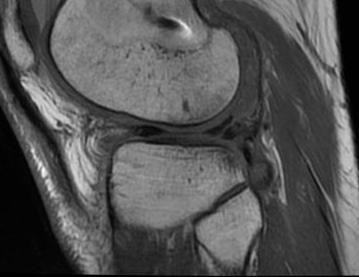

- used arthroscopy as gold standard to see if healed or failed repair

- MRI 90% sensitive, but up to 98% specific